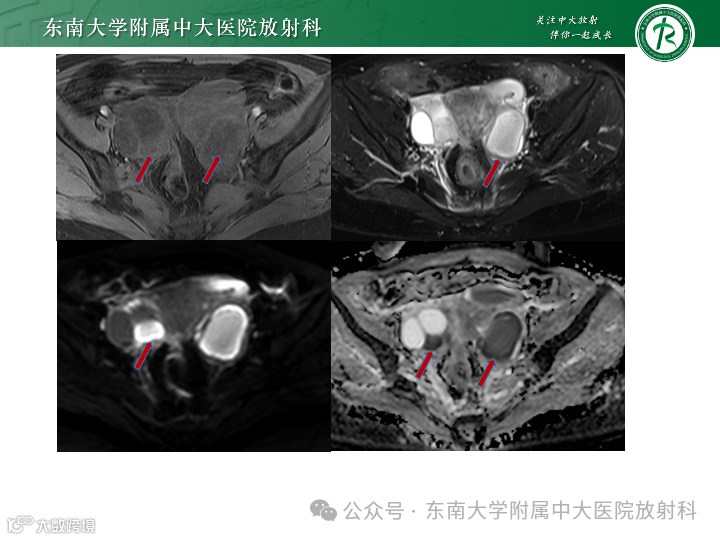

病例1

女,56岁 -

主诉:腹痛1月余 -

现病史:患者一月余前无明显诱因出现右上腹痛,伴有全身肌肉酸痛,自觉发热,体温未测,自行口服“白加黑”后全身酸痛好转,腹痛改善不明显,后口服“甲硝唑片”,腹痛稍有改善,深呼吸时加重,偶有头痛,食欲下降,遂至外院住院治疗,住院期间未予特殊治疗。现患者仍有上腹部疼痛,较前稍缓解,为进一步诊治来我院。患者无畏寒发热,无体重消瘦,否认“肝炎”、“结核”、“伤寒”等传染病史 -

实验室检查:

影像学表现